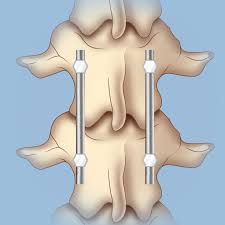

I tackled pt and the exercises and that was. After the first week, either ice or heat may be applied. Nonsurgical options include activity restrictions, physical therapy, and treating osteoporosis. There is a 3 mm retropulsion into the spinal canal, resulting in only mild canal. Fluoroscopic view of a kyphoplasty procedure. I have lumber compression fracture and i want to know how much time i need to rest in bed, currently im having totally bedrest even my wife gives me food by her hand only i standup for toilet so im in very depression and also demotiveted please help me someone does it heal by itself? This usually results from a combination of bending forward i suffered a compression fracture of the l2/l3/l4 vertebrae six years ago, and now i'm suffering with tremendous pain, discomfort and mobility. Vertebral compression fractures can be caused by a variety of reasons;

I have lumber compression fracture and i want to know how much time i need to rest in bed, currently im having totally bedrest even my wife gives me food by her hand only i standup for toilet so im in very depression and also demotiveted please help me someone does it heal by itself? This collapse can also cause pieces of bone to press on. Fluoroscopic view of a kyphoplasty procedure. In these situations, the fractures. Over the weekend i have been experiencing pins and needles in my right hand and arm, a sensation of someone pouring cold water on my left thigh and. At two months from injury, the fracture is probably still not fully stable as compression fractures take about 3 months to heal. Lumbar compression fractures can be a devastating injury, therefore, for 2 reasons. Are there effective ways to treat a compression fracture with physical therapy? The fracture looks like more of a compression fracture than a burst fracture (there is no retropulsion of the l1 body posteriorly). Anteroposterior and lateral radiographs of an l1 osteoporotic wedge compression fracture. Nonsurgical options include activity restrictions, physical therapy, and treating osteoporosis. Burst compression fracture of the l1 vertebral body is associated with a 35% loss of vertebral body height. Vertebral compression fractures (vcfs) occur when the bony block or vertebral body in the spine collapses, which can lead to severe pain, deformity and loss of height.